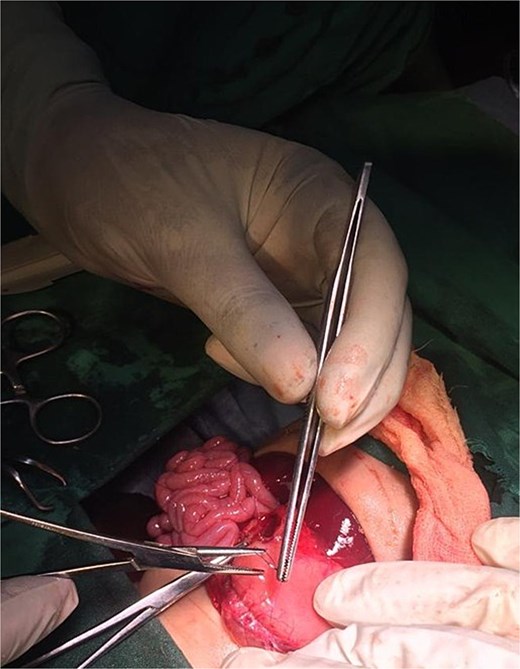

On the ninth day of life, the infant underwent exploratory laparotomy, which confirmed the diagnosis of Type I PA. A markedly dilated stomach with collapsed distal bowel was observed (Fig. 3). Pyloroplasty with transanastomotic nasoduodenal tube placement was performed (Figs 4 and 5). The nasoduodenal tube served as an alternative to parenteral nutrition, which was unavailable in our setting.